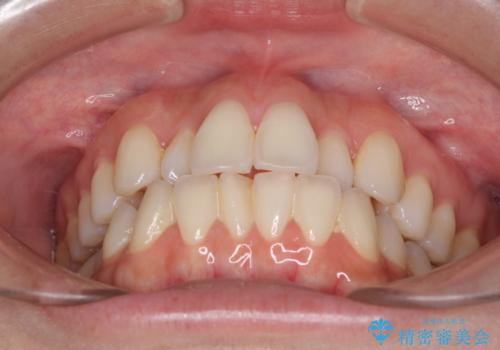

前歯のクロスバイト インビザラインによる矯正治療

- 上下のクロスバイトと前歯のデコボコを気にして来院された患者様です。

インビザラインを用い、IPR(歯と歯の間を削る)と歯列全体を拡大させることで、歯並びを整えていくこととしました。

治療を急いでいらっしゃらなかったため、のんびりと治療を進めていきました。3年以上の期間を要しましたが、きれいな口元に仕上がりました。